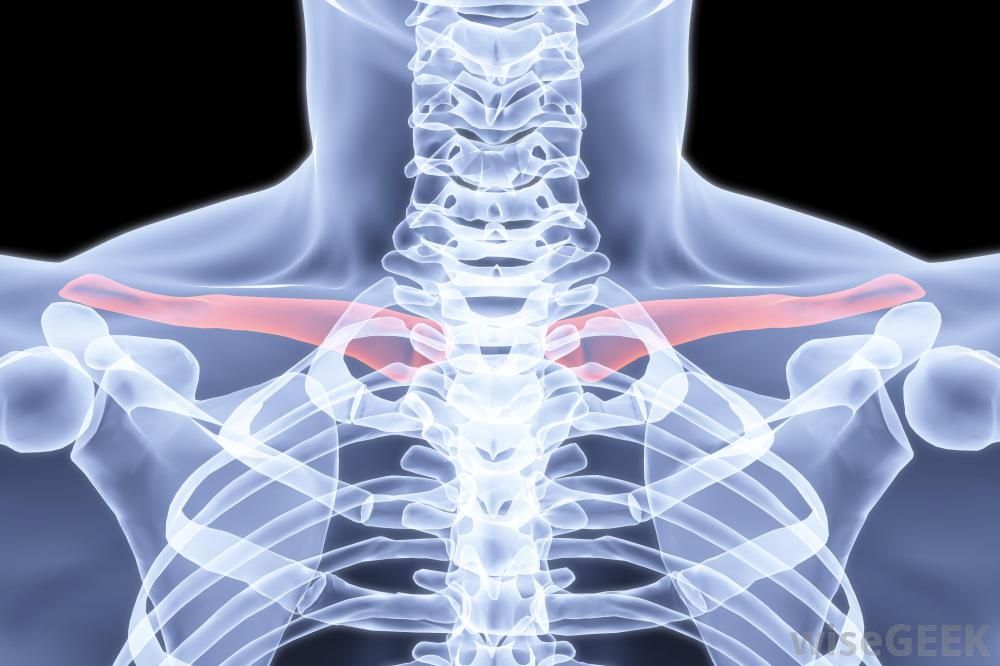

人的骨架,包括红色的锁骨。如果一个人觉得自己的锁骨断了,在去看医生之前,他应该尽量保持手臂不动。有时,骨折会导致开放性骨折,也就是说,当骨头穿过皮肤时。如果骨折处有伤口,可能意味着骨头打破了皮肤,但在患者移动时又重新进入。在这种情况下,患者应就医,因为手术可能是清理伤口和防止感染的必要手段。